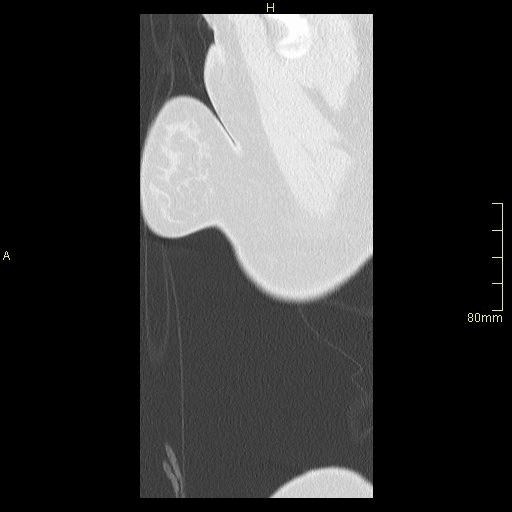

Example below is a General Chest/Abdo/Pelvis without contrast. Bony reconstructions are available depending on clinical question and differential diagnosis

Chest/Abdo/Pelvis (Sagittal)

Lung (Sagittal)